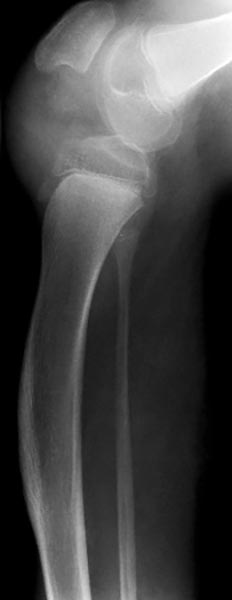

Seitliches Röntgenbild des linken Kniegelenkes mit Fehlwachstum von Ober- und Unterschenkel. Die Tibia hat in diesem Bereich im Wachstum eine Krümmung angenommen. Die Fibula steht dagegen gerade. Dennoch ist das wesentliche Problem auf das Kniegelenk beschränkt.